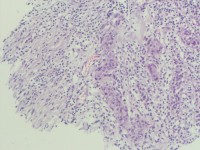

咔血3月,纤维支气管镜:右侧肺下叶基底段黏膜增生。能诊断肺部鳞状细胞癌吗?

鳞癌。